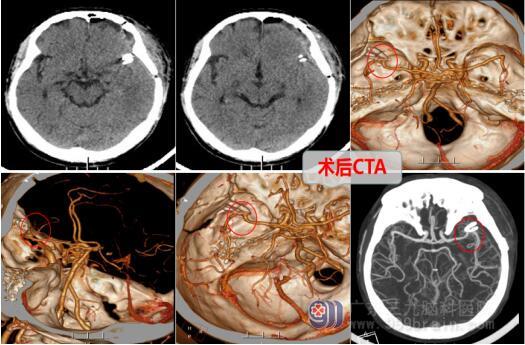

李先生果断的接受了医疗团队的手术方案,并在完善术前准备后,由欧阳辉教授为首的神经外十科团队为患者行左侧后交通动脉破裂动脉瘤夹闭术。经过几个小时的奋战,成功地完成了手术。术后的李先生精神良好,进入了下一阶段的治疗。

术后,李先生感叹自己犹如从鬼门关走了一趟,非常感谢神经外十科团队为他成功地夹闭了脑动脉瘤,这些医生是真正的“拆弹英雄”!